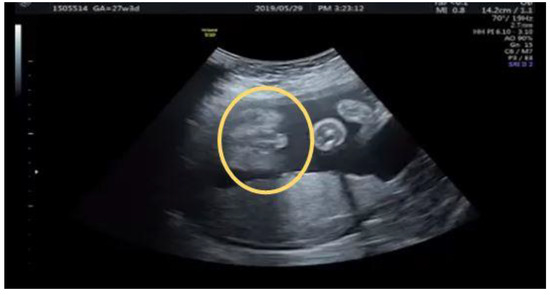

2.1. Case 1